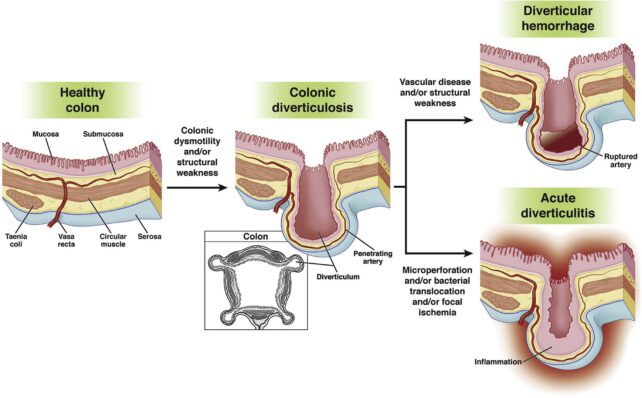

These sac-like protrusions along the digestive tract, called diverticula, are ‘weak spots‘ in the gut’s muscular wall. They are typically harmless, and most people never even know they are there.

Only if the pouches become inflamed or infected is it considered diverticular disease, or diverticulitis. Symptoms, which generally come and go, often include constipation, diarrhea, abdominal pain, bloating, or fever.

Once diverticula form, possibly from excessive pressure, they are prone to bleeding when aggravated, in a similar way to hemorrhoids, which form inside and outside the rectum and around the anus.

Diverticular bleeding is estimated to cause between 30 and 65 percent of all cases of lower gastrointestinal bleeding. It’s usually painless and self-limiting, but seeing blood in the stool is a serious matter, as it may indicate other severe conditions.

Surgery is only needed in severe cases – for instance, those in which an abscess forms or ruptures.